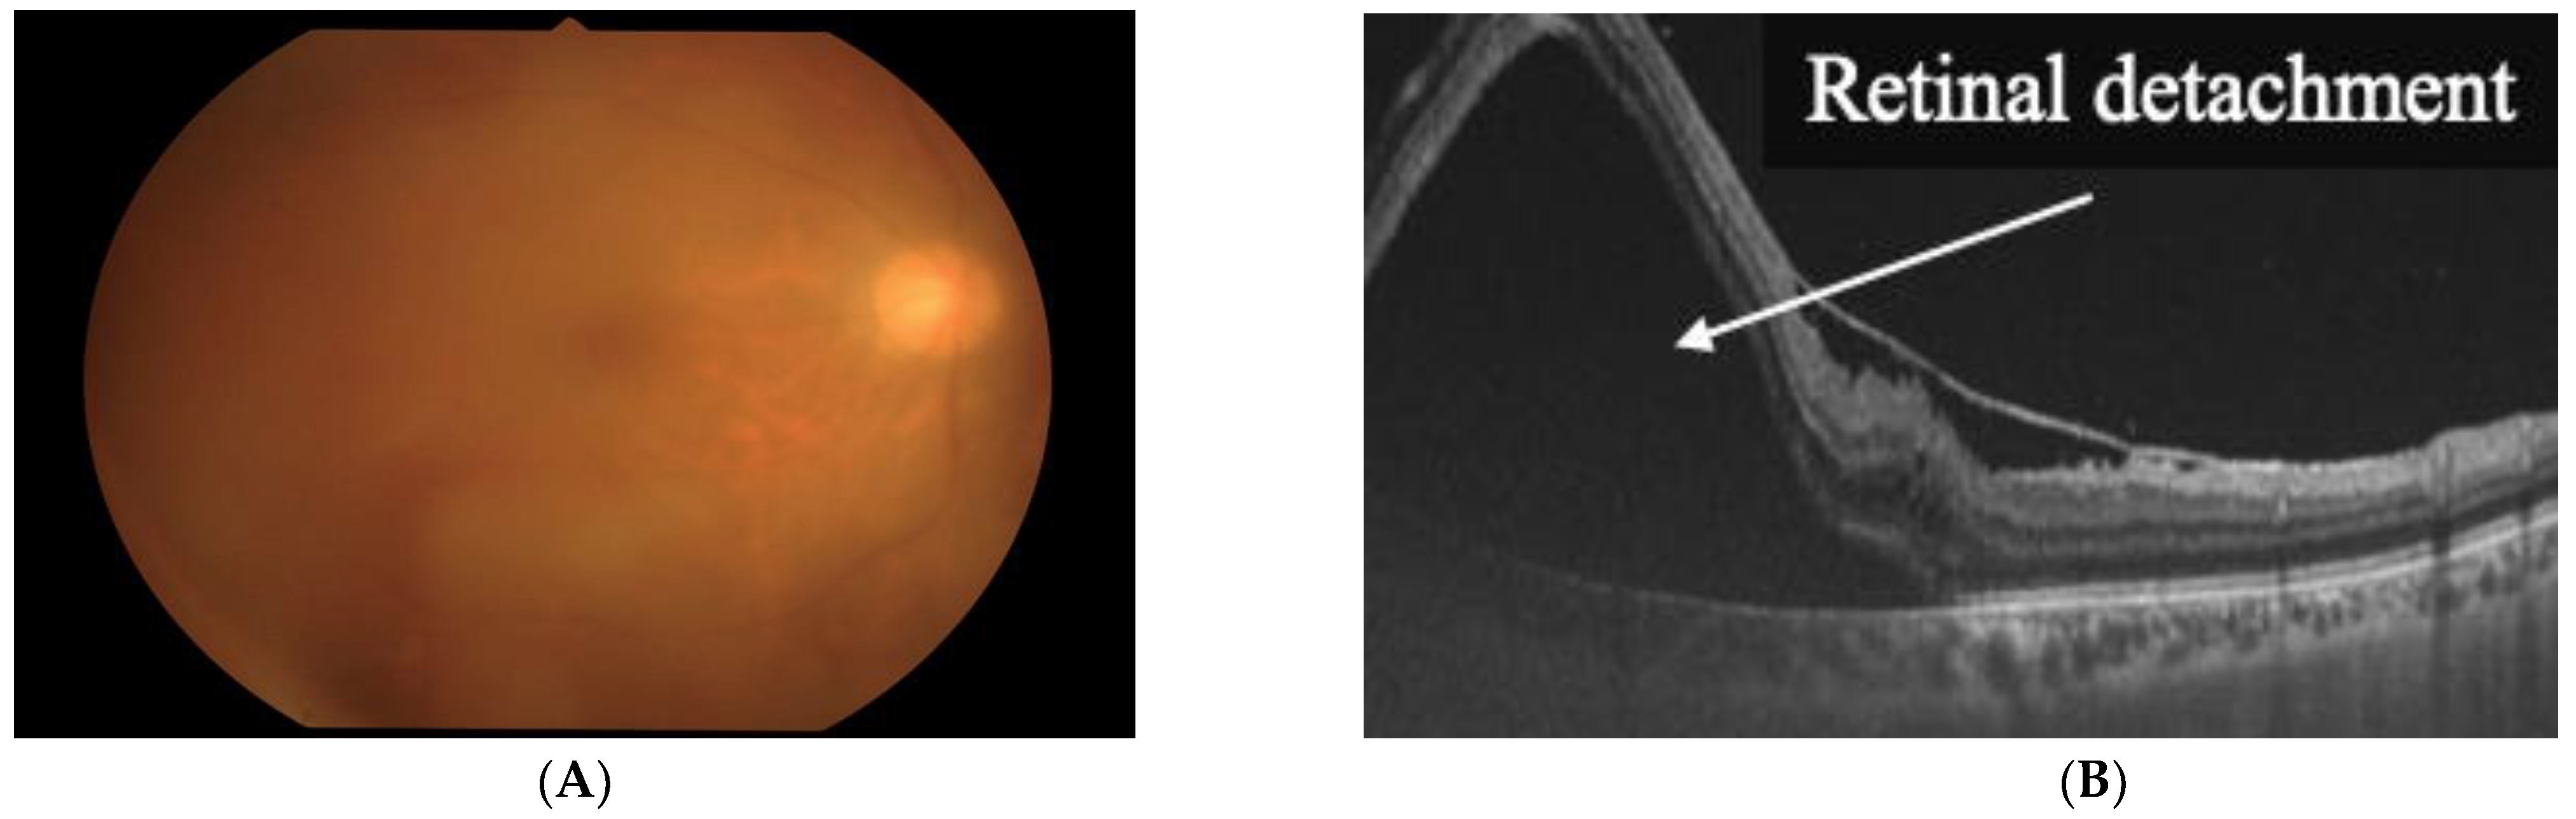

2. Clinical Features of HU